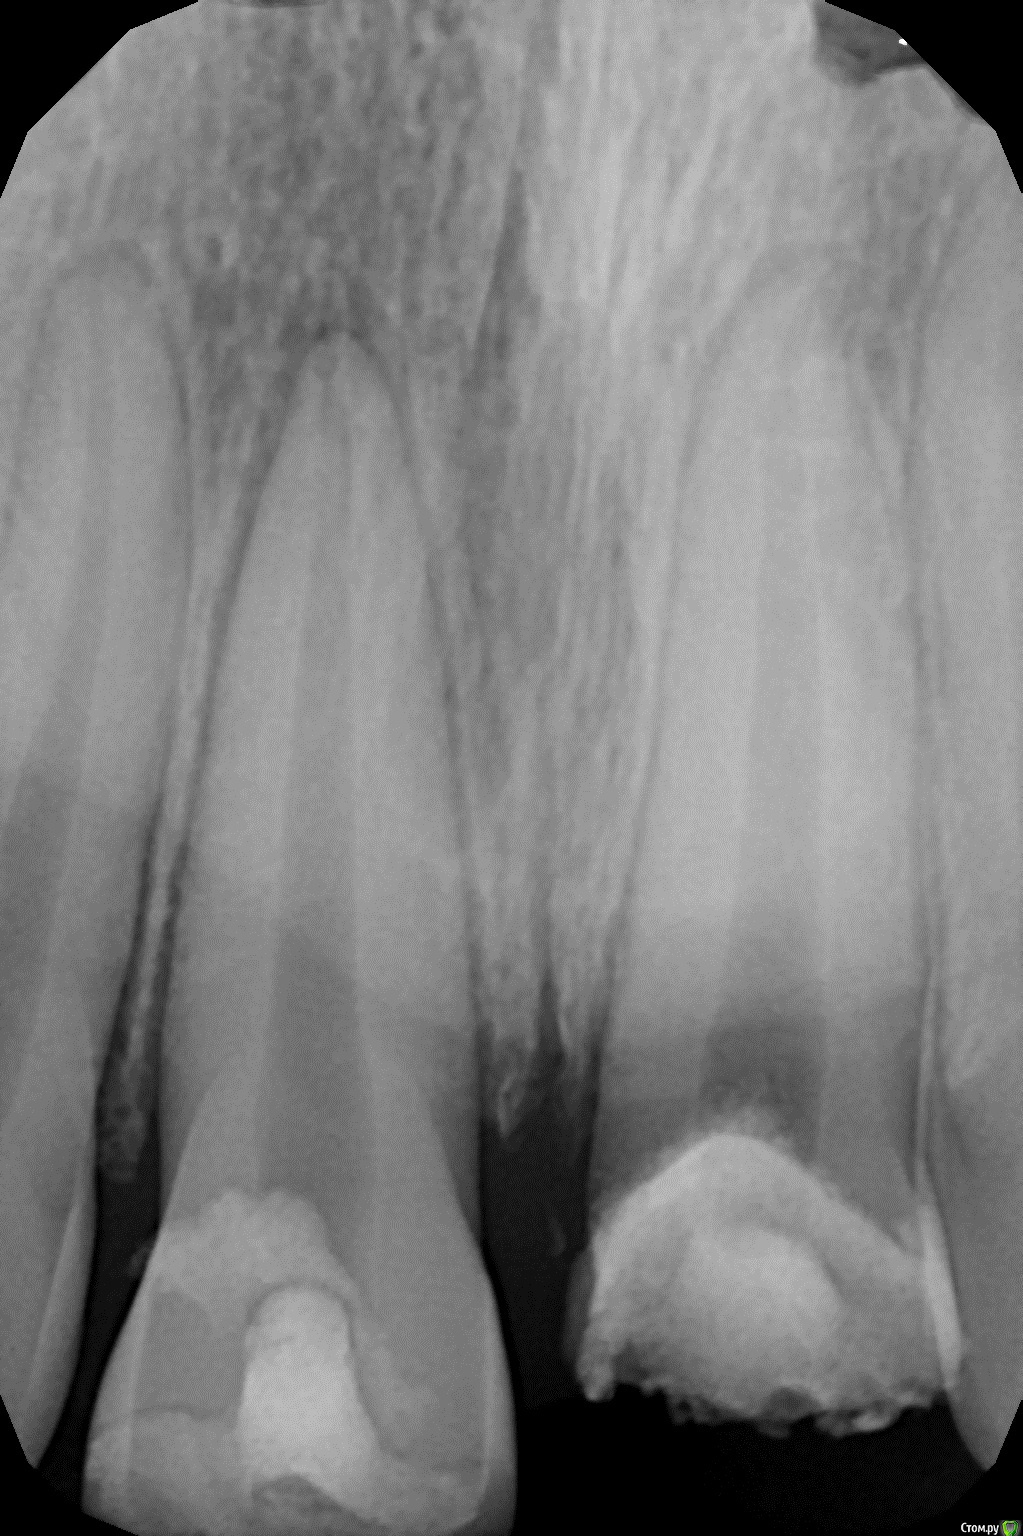

1586Doc Опубликовано 11 августа, 2017 Поделиться Опубликовано 11 августа, 2017 (изменено) Это обычная силиконовая каппа ?вытягиваем, потом стабилизация ? Как на долго? Изменено 11 августа, 2017 пользователем 1586Doc Ссылка на комментарий

kamranchick Опубликовано 11 августа, 2017 Автор Поделиться Опубликовано 11 августа, 2017 Это обычная силиконовая каппа ?вытягиваем, потом стабилизация ? Как на долго?капу сделали вакуум формером, помоему она пластмассовая вроде. стабилизация 2-3 месяца... Ссылка на комментарий